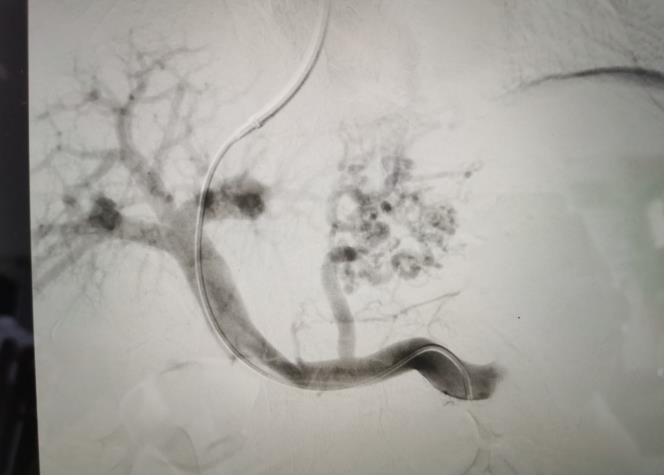

經(jīng)過我院血管介入科醫(yī)療團隊的精心準(zhǔn)備,患者在數(shù)字減影血管造影機(DSA)導(dǎo)引下,順利經(jīng)頸靜脈入路進入下腔靜脈并成功穿刺了門靜脈右支主干,術(shù)中栓塞了曲張的胃冠狀靜脈-食管靜脈叢將支架植入肝實質(zhì)內(nèi),支架兩端分別置于門靜脈和肝靜脈內(nèi),術(shù)程歷時2小時,術(shù)中患者時刻保持清醒,手術(shù)切口僅5毫米,術(shù)后第2天恢復(fù)飲食,腹脹、腹水癥狀明顯好轉(zhuǎn),未出現(xiàn)嘔血、黑便及肝性腦病等并發(fā)癥,術(shù)后第3天康復(fù)出院。